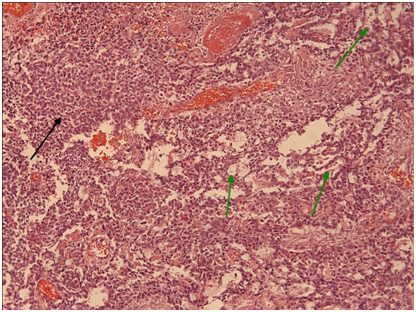

Figure 5 Mediastinal seminoma, like its gonadal counterpart, shows islands (green arrows) of large tumor cells with optically clear cytoplasm (due to large amounts of stored glycogen). These islands are separated by fibrous septa (black arrows) heavily infiltrated by non-neoplastic lymphocytes. (H + Ex10).

Figure 9 Yolk sac the microcystic / macrocystic reticular pattern of growth (green arrows) is the most common finding in yolk sac tumors (>70% of cases).Nevertheless, it is possible to encounter more solid areas (black arrow). (H+E,x4).